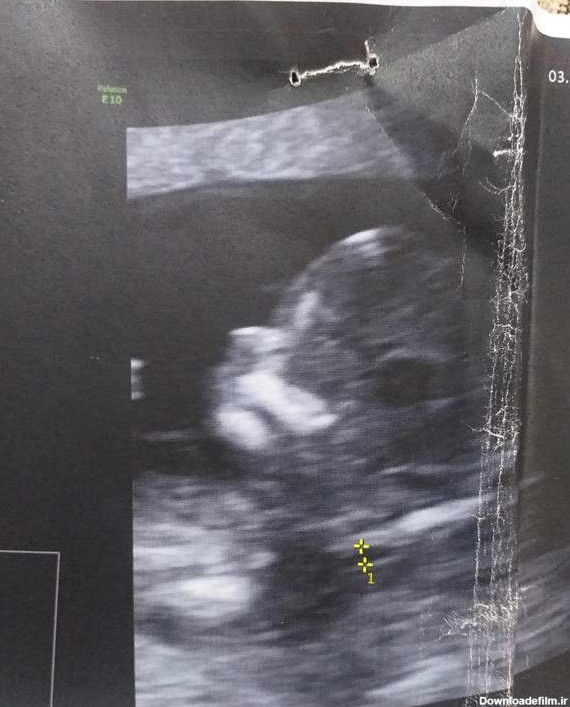

سلام دوستان.میتونید جنسیت رو تشخیص بدین با جمجمه نوزاد؟ شبیه پسر پسر پسره منم یه هفته دیگه سونو دارم😍

کسی میتونه از رو جمجمه بگه نی نی چیه پسر چطوری تشخیص میدی هر چی حدس بزنن ممکنه اشتباه باشه اگه عجله داری ۱۶ هفته سونو برو دکتر نگفت احتمالا دختره یا پسر

هر کسی واقعا بلده و همیشه جوابش درست بوده جنسیت نی نی من رو از سونوی nt بگه لطفاً...میدونم باید صبر کنم واسه آنومالی اما چه کنم که بعد از سال مامان شدم و صبر ند